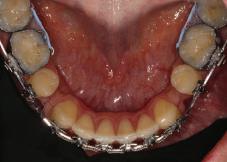

Пациентът постъпи в клиниката с молба за тотална рехабилитация на усмивката. Той не харесваше централ ните си резци, които според него бяха твърде къси и квадратни. Имаше раз стояние от медиално и дистално на латералните му резци. Друго сериоз но оплакване бе свързано с металоке рамичната корона на зъб 12, която бе жълтеникава и неестетична, като цяло не харесваше вида на венците си и както самият той се изразяваше, „вижда се прекалено много от венците при усмивка“.

След диагностиката бяха направени екстра- и интраорални снимки, както и рентгенографии; професионалното почистване бе от изключителна важ ност, бяха дадени и инструкции за лич на орална хигиена. Бе направено интра орално сканиране с Medit i500. Цялата тази информация бе използ вана в приложението Smilecloud за 2D биометричен дизайн. В приложението са налични естест вени форми на зъбите и щом бяха под брани зъби и бе направен дизайн

библиотеката на Exocad. Струва си да се отбележи, че 2D дизайнът от Smile Cloud бе спазен до последния детайл в Exocad smile creator с цел да се създаде 3D obj файл със зъбните форми. След като естетичният дизайн бе готов в model creator модула на Exocad, адитивен 3D мок-ъп модел бе експорти ран и принтиран от принтер Formlabs 3. Моделът бе използван за направата на силиконов водач, за да се изготви мо тивационен мок-ъп в устата на паци ента и да се оценят естетичните па раметри. След като пациентът одобри вида на усмивката си, мок-ъпът бе използван за финализиране дизайна на усмивка та. Мок-ъпът бе използван също така като водач по време на мекотъканна та хирургия, както и при препарация на зъбите.

Препарираните зъби бяха импорти рани в Exocad и насложени върху ес тествените форми от биометричния дизайн, като така стана ясно дали зъ бите са били препарирани коректно. По този начин зъболекарят и зъботехни кът работят в една и съща екосистема и резултатът е оптимален. С короната се справихме чрез диги тална редукция на циркония в Exocad, като по този начин на практика създа дохме циркониево кепе, след което про изведохме фасета от IPS Empress Cad Multi. Кепето от Katana Zirconia на зъб 12 с букално послойно нанесена керами ка бе фрезовано (послойното нанасяне бе направено, за да се подобри връзката и да се осигури адхезивно циментиране на фасетата към циркониевото кепе, както и за да се напасне цветът към този на съседните зъби). При първото сканиране регистрирах ме цялата горна зъбна дъга, така че, ко гато се наложи да сканираме повторно, бе изтрит и сканиран наново само зъб 12, тъй като венците не бяха отдръп нати при второто сканиране.

НА

рентгенографии. Инициална терапия и професионално почистване. Интраорално сканиране с цел диги тално планиране. Регистрация и 3D ориентиране на ок лузалната равнина на горна и долна челюст в пространството. 2D дигитално планиране и дизайн на усмивката посредством приложение то Smile Cloud. 3D дигитално планиране и дизайн на функционалните и естетичните па раметри. 3D дигитален дизайн и адитивен мокъп на горна челюст. 3D принтиране и мок-ъп модели. Мотивационен мок-ъп. Фини корекции за постигане на фи налния дизайн. Мекотъканна хирургия с мок-ъпа като водач Препарация през мок-ъпа, използвай ки дизайна като водач за финалната препарация в Exocad. Циркониево кепе ще бъде циментира но с цел адхезивно залепяне на фасе та на края. Кепето има същия цвят като този на съседните зъби, за да може фасетата да се впише перфект но в цялостната усмивка. Изработване на 12 IPS Empress Cad Multi фасети с послойно нанесена ке ТОТАЛНА РЕХАБИЛИТАЦИЯ НА УСМИВКАТА С ИЗЦЯЛО ДИГИТАЛЕН ПРОТОКОЛ Д-р Калин Маринов и зт. Стефан Петров рамика букално върху зъбните препа рации и върху първичното циркони ево кепе (има възможност за ецване и адхезивно

Една седмица след препарацията на зъбите и циментирането на цирко ниевото кепе бяха изработени 12 IPS Empress Cad Multi фасети. Макро- и микротекстурата на фасе тите бяха направени на ръка, след кое то бяха нанесени 3D характеризации с боички, а полирането отново бе напра вено ръчно, за да им се придаде естест вен и естетичен вид. Предизвикателството тук беше короната да има същите оптични характеристики като тези на остана лите зъби при естествена светлина, през поляризационен и флуоресцентен филтър. 3D принтерът бе Fromlabs, софтуерът за фрезоване – Mill Box, а фрез апаратът –imes icore CORiTEC 350i. В крайна сметка постигнахме ес тествен вид на усмивката с натурал на зъбна морфология при изцяло диги тален протокол, при който дизайнът бе направен първоначално и през всич ки етапи на лечението се придържахме към него до самия край Излишно е да отбелязваме, че всички сме удовлетворени от постигнатото! Преди След Победител в категория „Клиничен случай с изцяло дигитален протокол“ в конкурса „Усмивка на годината 2022“

11Dental Tribune Bulgarian Edition / октомври 2022 г. Преди лечението Фиг. 1 Фиг. 2 Фиг. 3 Фиг. 4 Фиг. 5 Фиг. 6 Фиг. 7 Фиг. 9 Фиг. 10 Фиг. 11 Фиг. 8 Фиг. 12 Фиг. 13